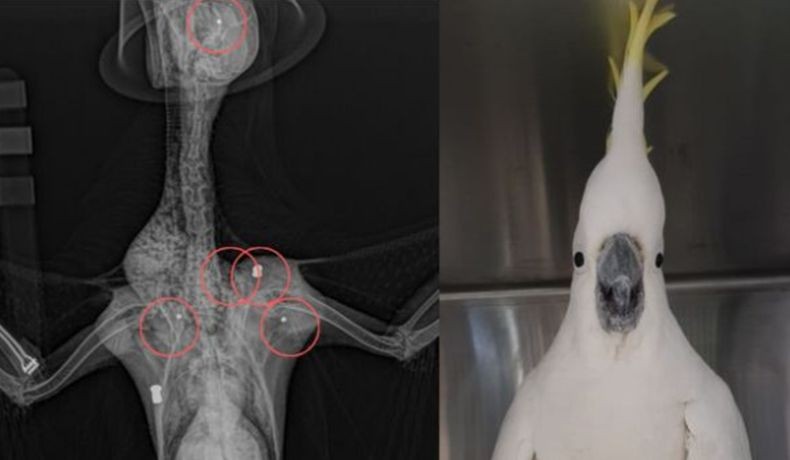

Kakatua selamat meski ditembak 5 kali (Foto: Avian Reptile and Exotic Pet Hospital)

SYDNEY, iNews.id - Seekor burung kakatua di Sydney, Australia, selamat meskipun ditembak lima kali menggunakan airsoft gun.

Kakatua jambul kuning yang kemudian diberi nama Cocky itu ditemukan terkapar di jalanan Kota Sydney oleh masyarakat pada bulan lalu kemudian dibawa ke klinik hewan setempat Avian Reptile and Exotic Pet Hospital.

Menurut klinik, ada beberapa gotri yang masih bersarang, termasuk satu yang lokasinya hanya beberapa milimeter dari mata kiri. Beberapa peluru sudah diambil dan kini Cocky menjalani fisioterapi agar bisa aktif kembali.

Hasil pemindaian x-ray mengungkap, tiga gotri lain bersarang di dada dan satu di pundak. Tampaknya hewan yang dapat menirukan suara manusia itu ditembak menggunakan senapan berbeda.